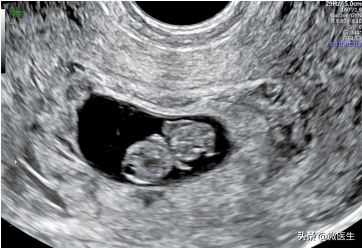

(2)卵黄囊:妊娠囊内第一个能观察到的结构是卵黄囊,发现卵黄囊即可确认妊娠。卵黄囊是圆形线状强回声,内充满液体。经腔内超声检査,孕5周左右显示卵黄囊:经腹部超声检査,孕6周左右显示卵黄囊(下图)。卵黄囊直径3~8mm,卵黄囊过大(直径10mm)或过小(直径3mm)或变形、内部出现强回声等,预示妊娠结局差。

孕7周,经阴道超声检查显示卵黄囊(粗箭头)羊膜(长箭头)、胎芽(细箭头)、妊娠囊

孕8周,经腹部超声图像卵黄囊(粗箭头)、羊膜(长箭头)、胎芽(细箭头)